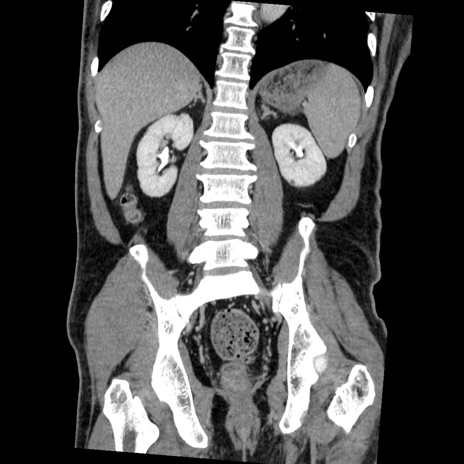

症例22(冠状断像)

【症例】50歳代男性

【主訴】腹痛

【現病歴】AVMからの被殻出血のため回復期リハ病棟入院中。 本日午後3時頃急に下腹部痛が出現した。

【既往歴】AVM、被殻出血、虫垂炎、高血圧

【身体所見】意識晴明、左半身不全麻痺、会話の理解は良好、36.5°C、腹部:膨隆、全体に板状硬、下腹部正中に圧痛点あり、反跳痛-、筋性防御不明、右下腹部にope scar

【データ】WBC 9400、CRP 0.06